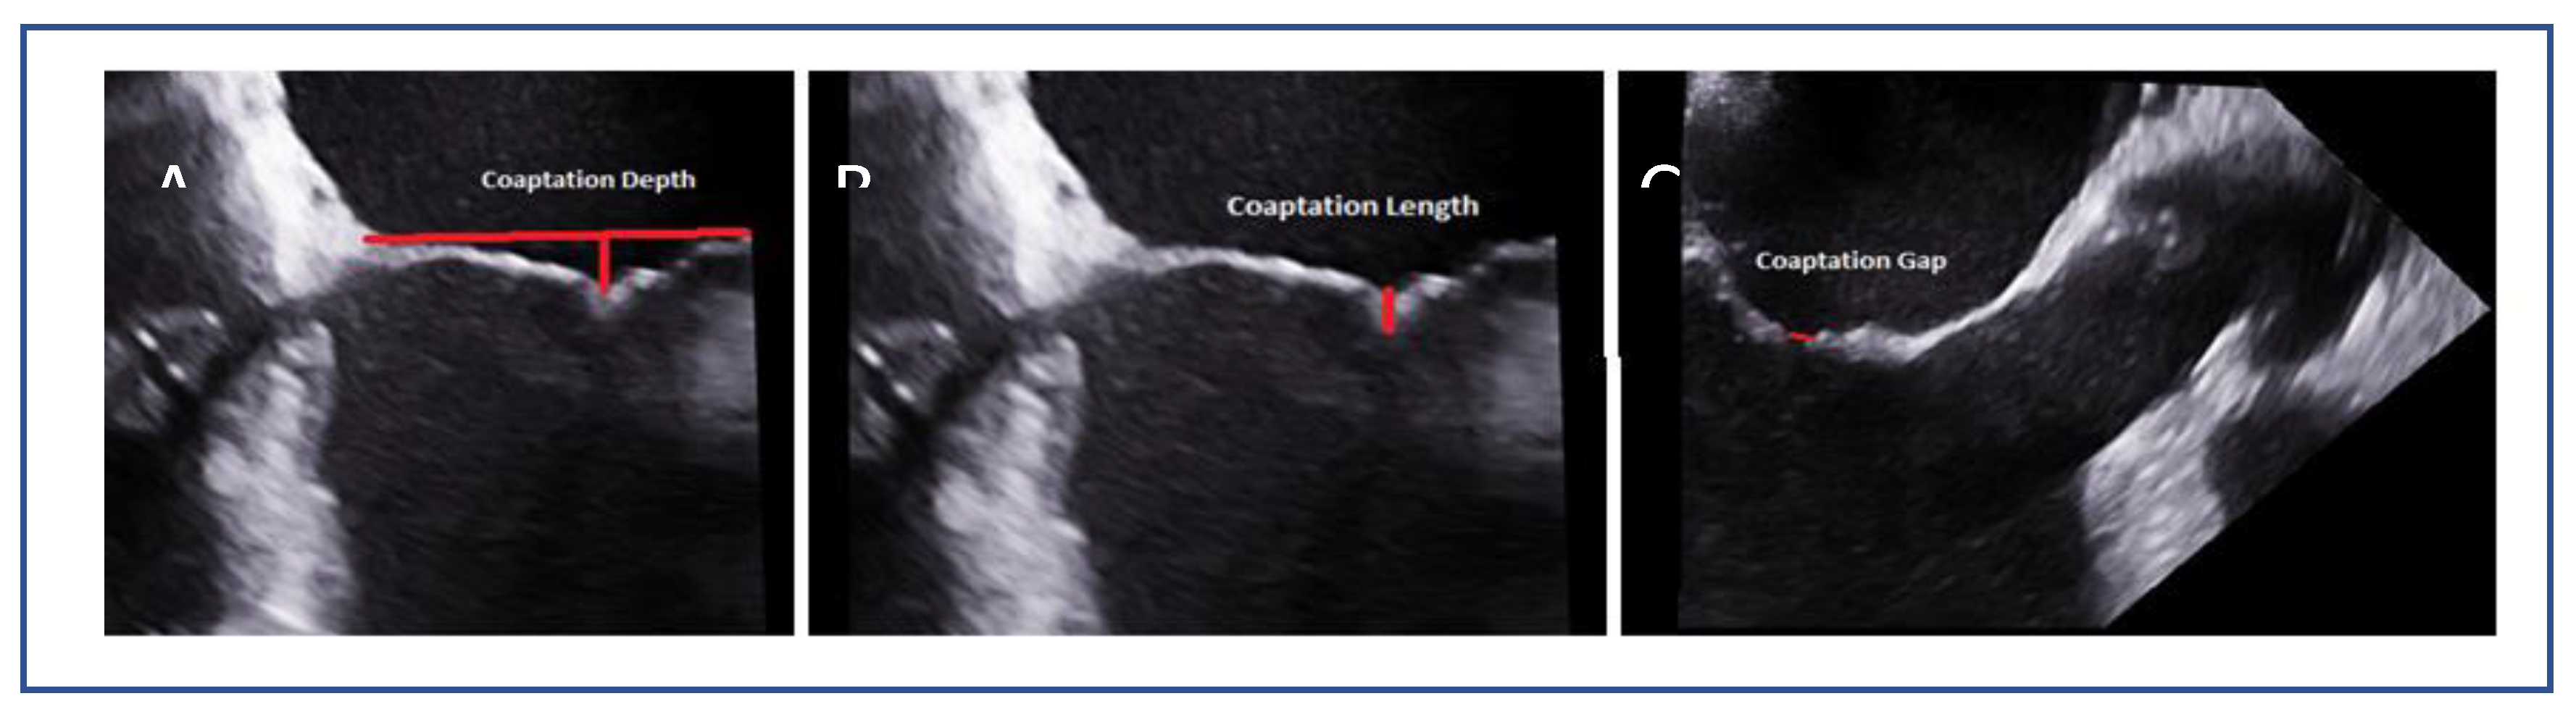

- Coaptation depth and coaptation length: Excessive coaptation depth (>11 mm) or reduced coaptation length (<2 mm) may pose procedural difficulty in secondary MR.

7.5. Tenting Height and Coaptation Length (SMR)